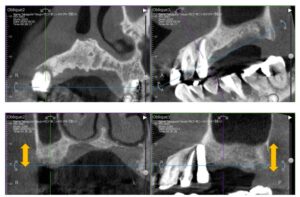

右上は骨のある5番目の歯にはすぐに埋入できましたが、奥は抜歯したら骨が残ってなくて骨を造ることから始めました。上が抜歯後すぐで下がGBRしたあとです。

インプラントが入った状態で再度スプリントを入れて顎の位置の確認をしました